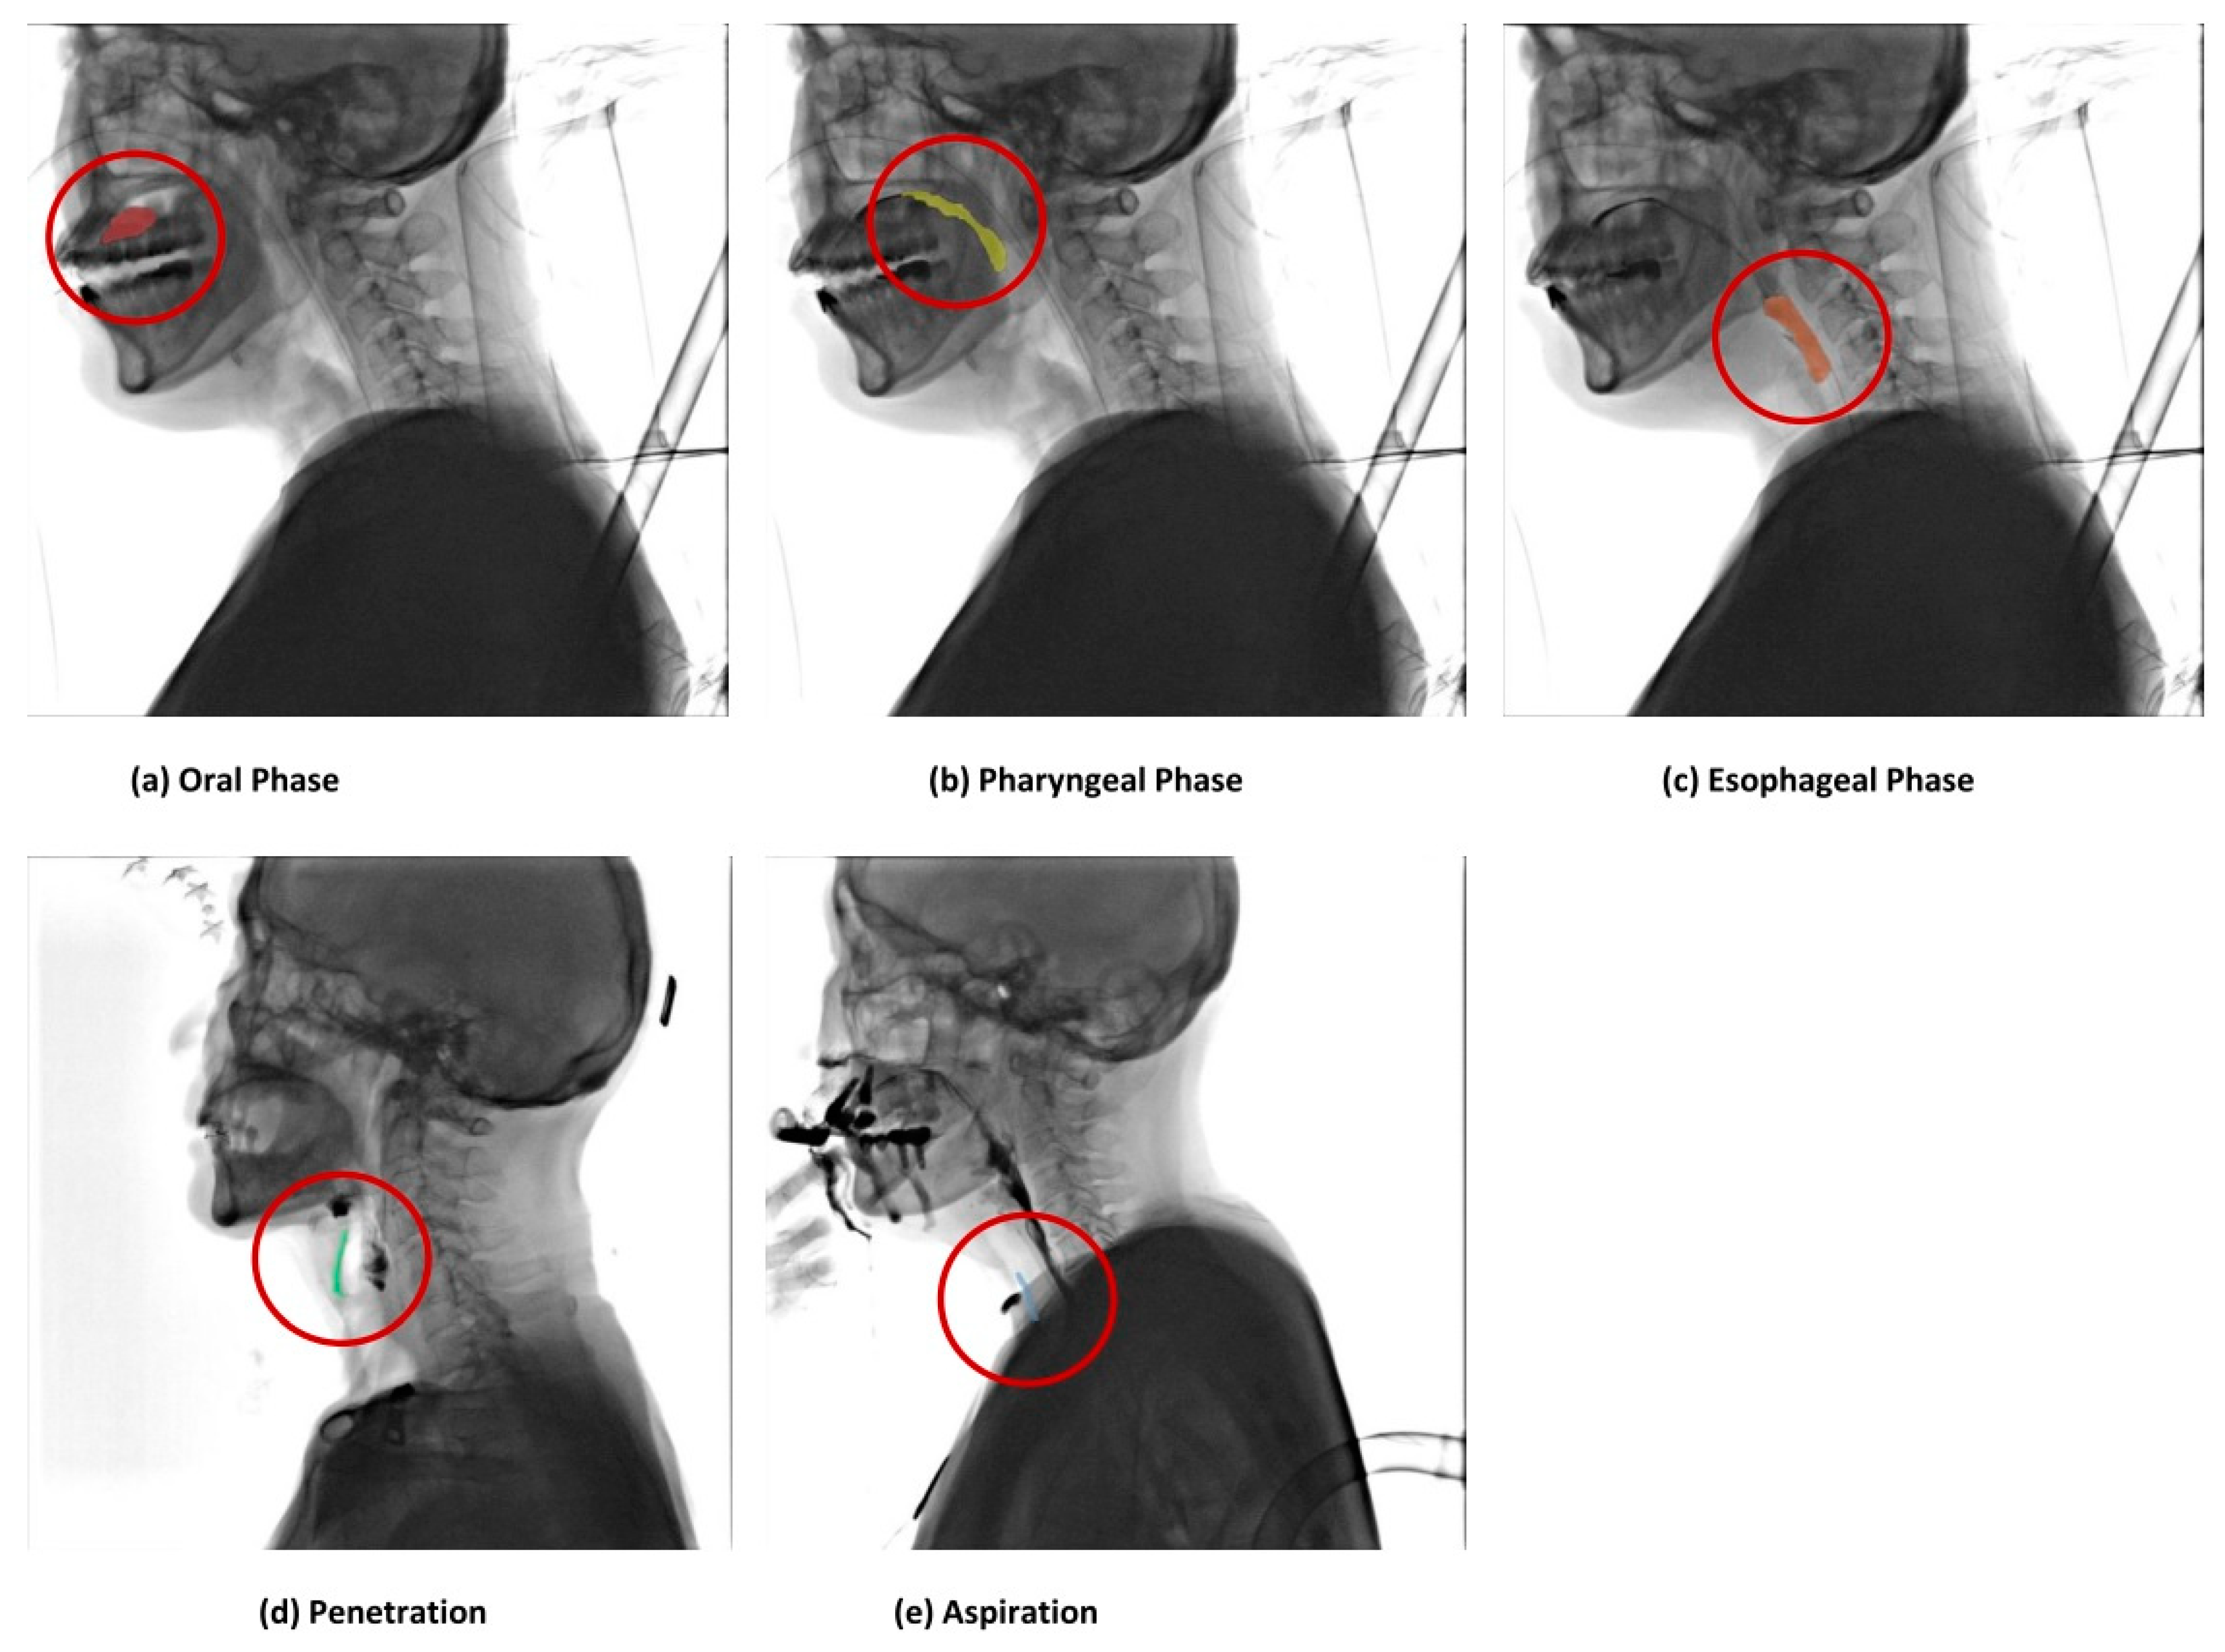

Each stage in which the food material (a bolus) moved from the oral phase to the pharyngeal phase and the esophageal phase was labeled, and the bolus corresponding to penetration and aspiration was labeled [20]. After defining the boundary part of each phase in advance, three technicians performed the labeling. At this time, there may have been some differences in boundary classification due to anatomical variation among each technician. In this case, the boundary classification and labeling were conducted according to the opinions of clinical experts. Oral, pharyngeal, esophageal, penetration, and aspiration were divided into five classes, and each class was labeled as oral (n = 2355), pharyngeal (n = 2338), esophageal (n = 1480), penetration (n = 1856), and aspiration (n = 1320).

The AI training was tested in two ways. First, for a comparison with related studies [19], a CNN-based classifier, an AI model that classifies each class, was trained using EfficientNetV2 [16]. Then, using YOLOv7, we developed an AI model for object detection for each class [21]. As a result of experiments under similar conditions, the training time and performance of the YOLO model were proven, and the YOLO model was chosen as the leading AI engine. The model used data with the original image size and showed a good performance in terms of training time and accuracy performance. In addition, it had the advantage of being able to check the object to be diagnosed in real time in this study. In the VFSS video, it was the leading model for the real-time tracking of food masses from the mouth to the esophagus. Figure 7 shows the outcome of predicting the VFSS inspection data without any training data.

The food material was automatically detected and identified as each frame moved quickly, and Figure 7a represents the detection of the food material in the oral stage. Figure 7b shows the detection of the food material in the pharyngeal phase. Similarly, Figure 7c represents the detection of the food material in the esophageal stage, and Figure 7d shows the detection of the food material corresponding to aspiration. Finally, Figure 7e shows the detection of the food material corresponding to penetration.

Figure 5. The results of labeling the food material by the user interface of the medical labeling web application. The results of labeling the food materials by the phase are shown. The results of labeling food materials in the normal state in the (a) oral, (b) pharyngeal, and (c) esophageal phases are shown, and the results of labeling (d) penetration and (e) aspiration in the dysphagia state are shown.